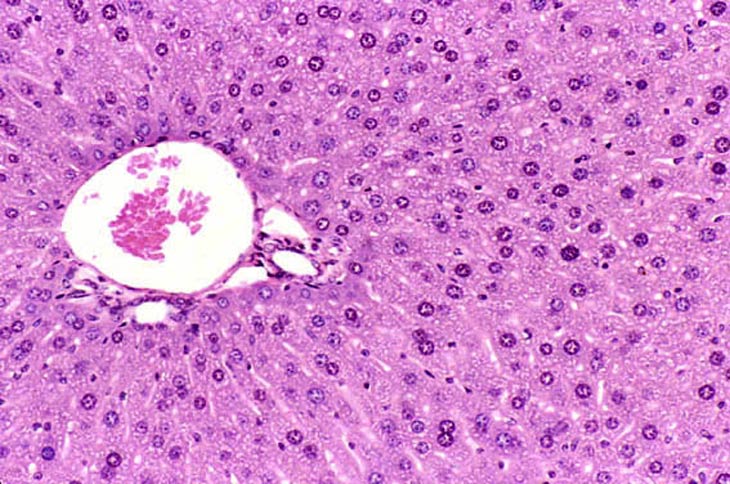

The normal mouse liver contains hepatocytes that are diploid, tetraploid, and octaploid with increase ploidy occurring as the animal ages. A tetraploid hepatocyte may have twice the complement of DNA either by having two diploid nuclei (binucleated hepatocyte) or a single nucleus which contains twice the diploid amount of DNA. A variety of treatment regimens cause alterations in ploidy with single hepatocytes sometimes having several diploid nuclei (multinucleated hepatocytes). The hepatocyte regeneration that follows partial hepatectomy is the result of proliferation of diploid cells. Polyploidy develops once the liver has completed regeneration.

Normal mouse liver showing a mixture of diploid, binucleate, and tetraploid hepatocytes.